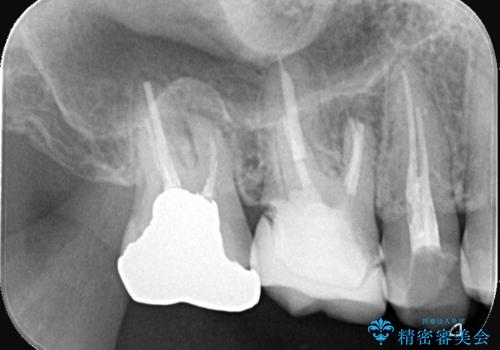

- 「銀歯を白くしたい」が主訴の患者様です。

銀歯を除去後、オールセラミッククラウンで治療を行いました。

被せ物のやり変えのみ希望だったため、根管とコアはさわっていません。

銀歯と虫歯を除去後、オールセラミッククラウンで治療を行いました。